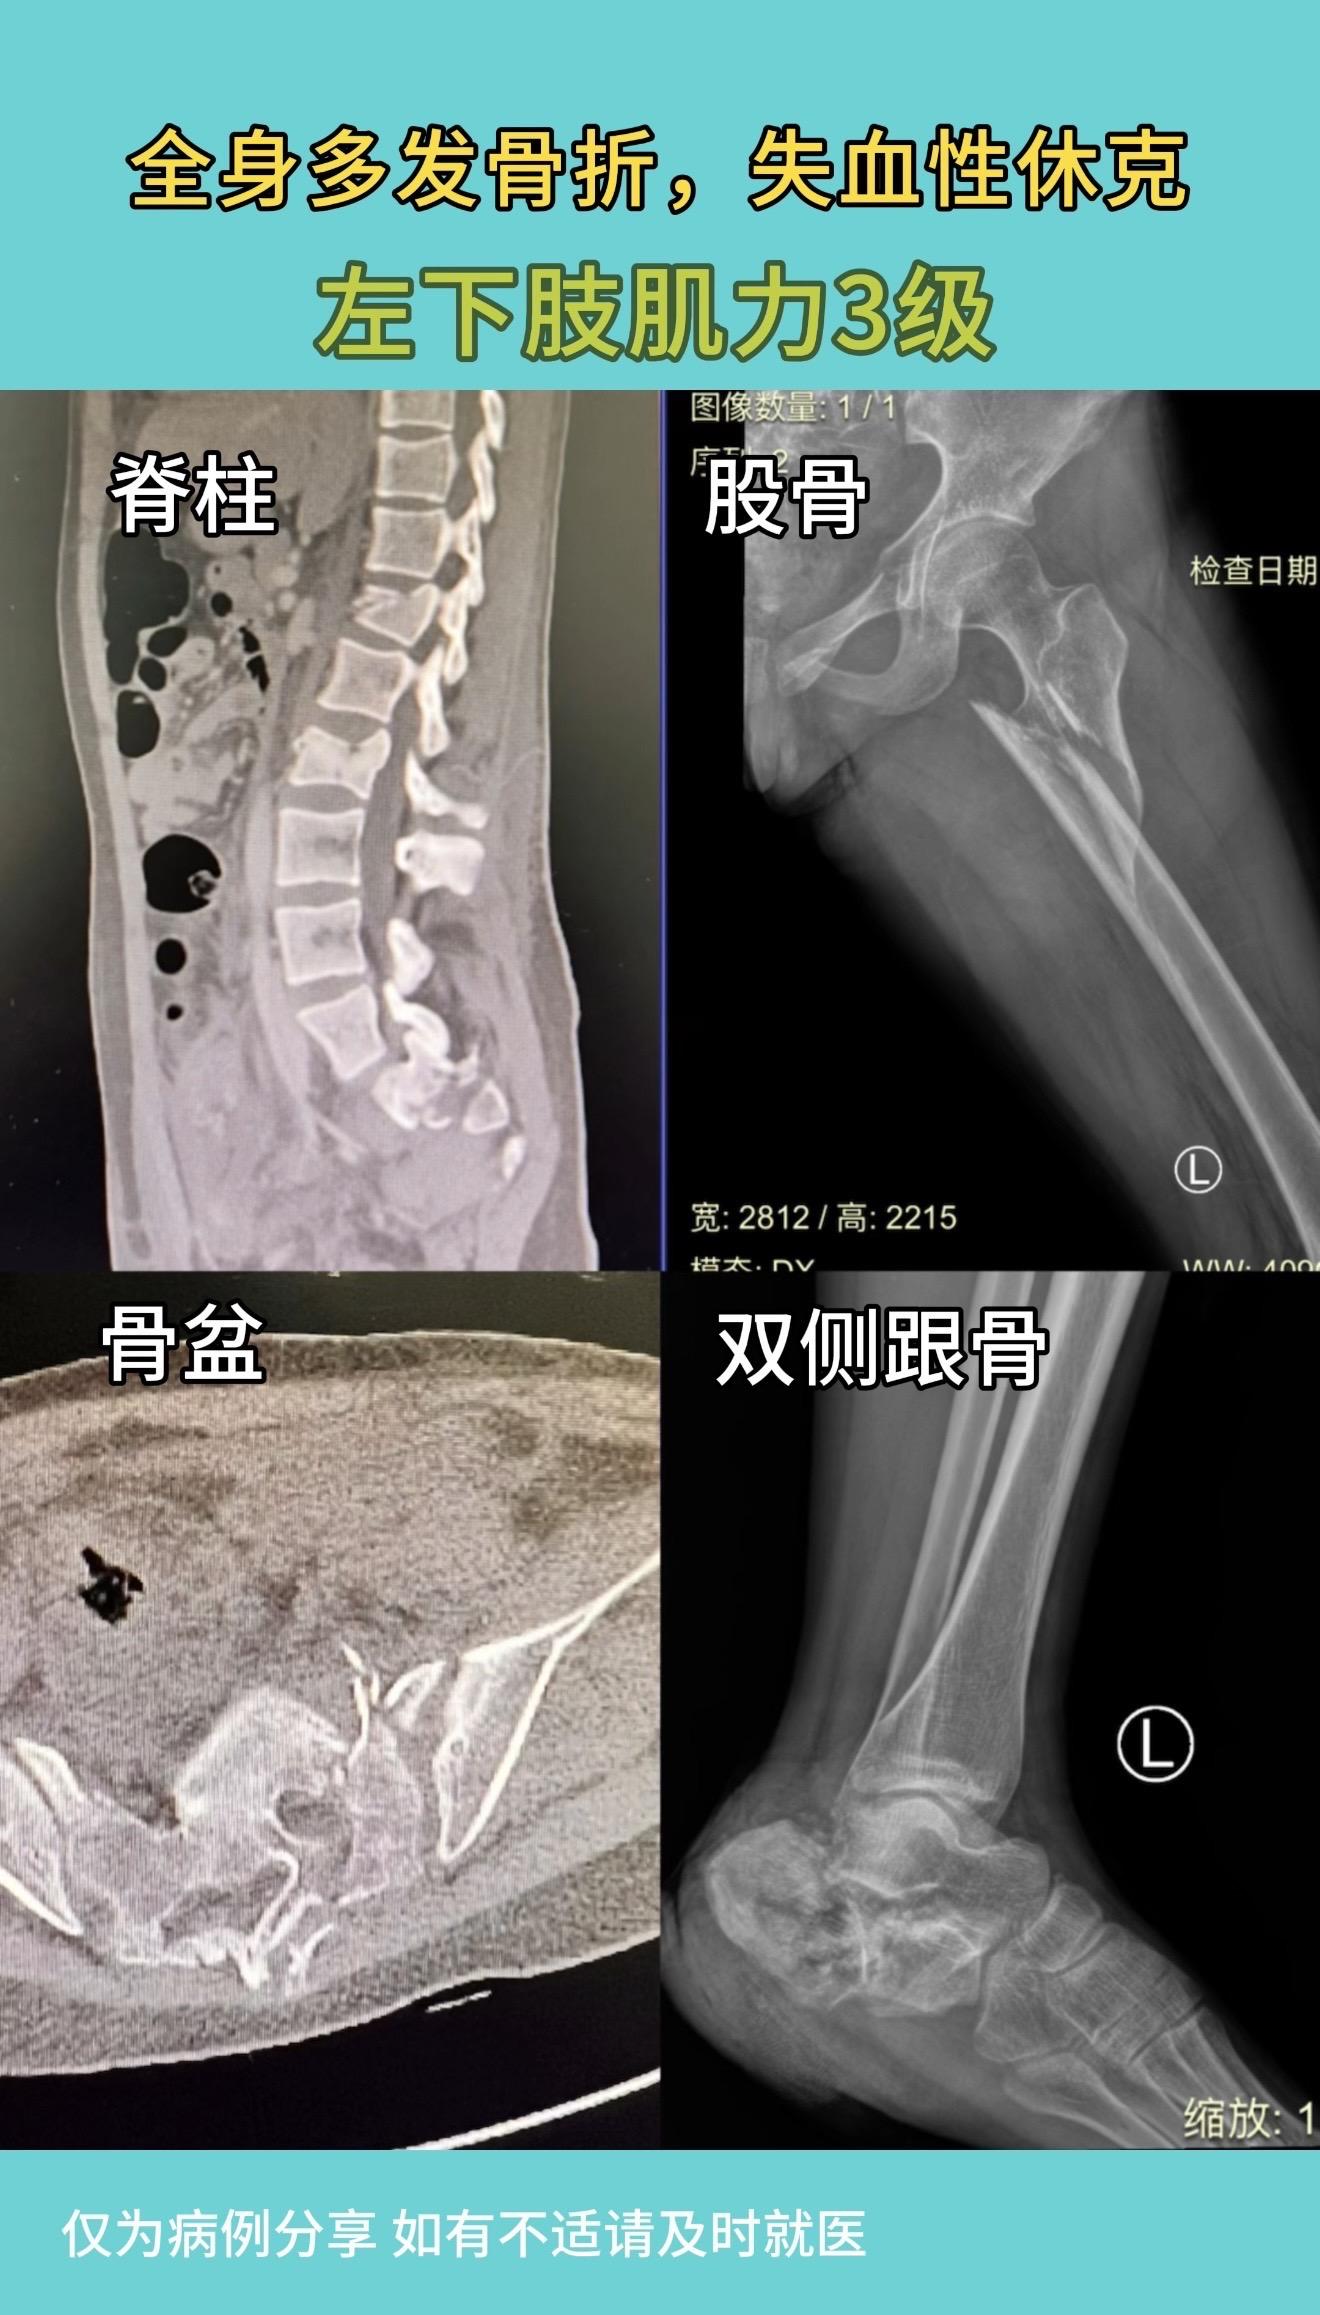

女孩因家人管教,被限制外出,竟“奇思妙想”,仿电影情节,拿一根较细绳子从7楼家中窗户“下楼”,绳子下降到3楼时断裂,摔成重伤。入院后积极治疗,生命体征稳定后,手术治疗,各部位骨折复位满意。左下肢肌力恢复至4级。